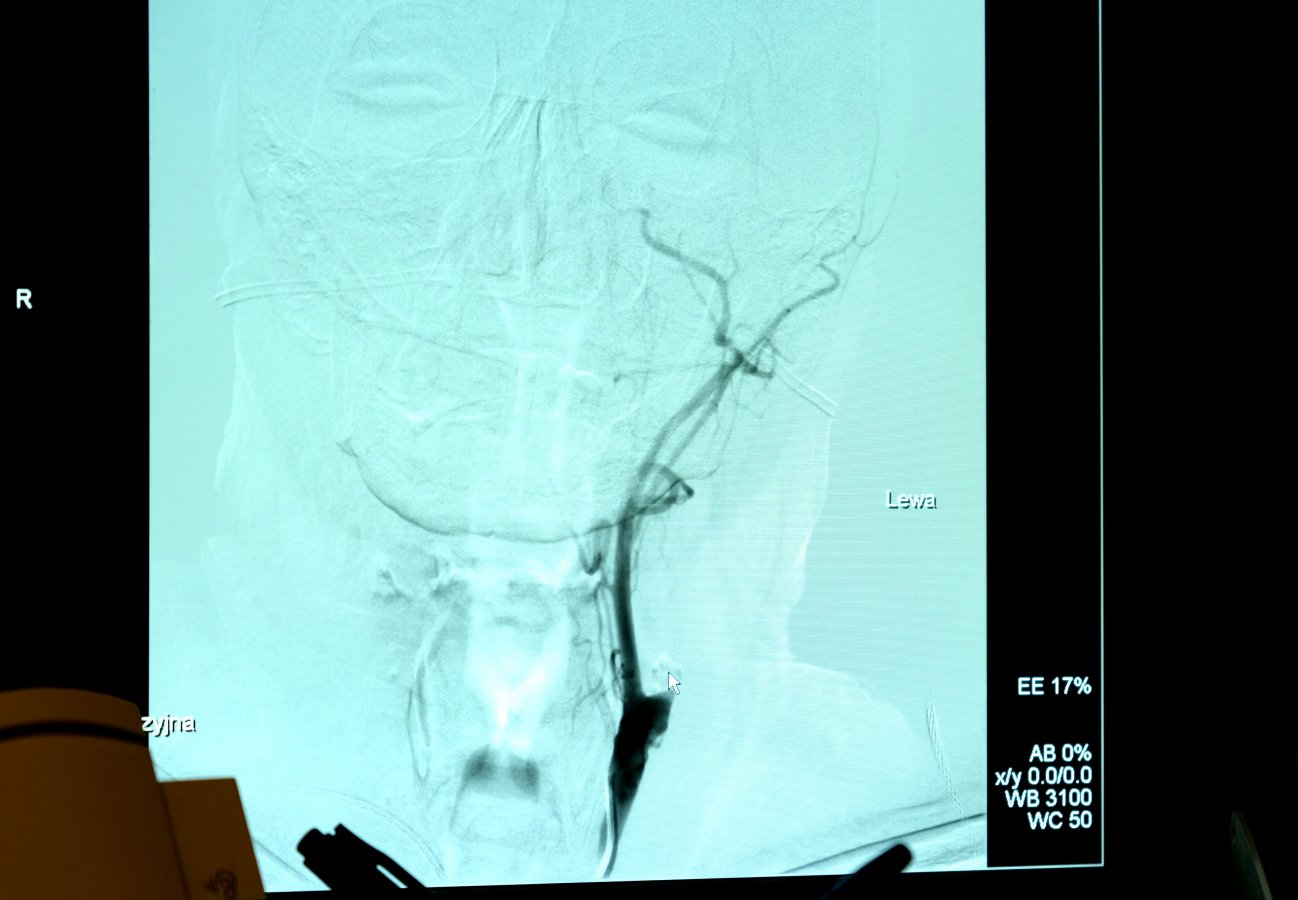

Dotychczas udar leczony był poprzez podanie dożylnie leku trombolitycznego, którego zadaniem było rozpuszczenie skrzepu. Lek można podać maksymalnie do 4 godzin i 30 minut od wystąpienia objawów. Dodatkowo nie wszyscy pacjenci kwalifikują się do tego typu leczenia. Dzięki trombektomii lekarze mogą dotrzeć przy pomocy cewników do wnętrza tętnicy mózgowej, znaleźć skrzeplinę poudarową, a następnie mechanicznie ją usunąć (taki zabieg miał pan Edmund). Zabieg odbywa się w Zakładzie Radiologii Zabiegowej pod kontrolą angiografu i trwa ok. 40 minut. Co istotne, pacjent musi trafić na zabieg w ciągu 6 godzin od wystąpienia objawów.